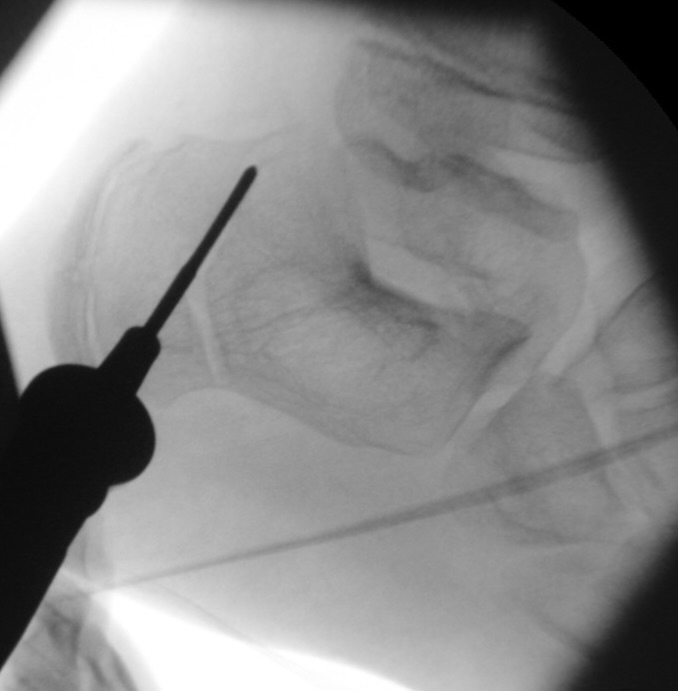

=> Risikoabwägung der radiologisch leicht erhöhten Strahlenbelastung intraoperativ

In der minimalinvasiven Fußchirurgie ist es unabdingbar, die Fräse in ihrer Position zum Knochen radiologisch zu kontrollieren, damit vulnerable Wachstumsfugen oder angrenzende Gelenke nicht verletzt werden. Zu diesem Zweck werden mit einem Bildwandler während der Operation die genaue Position der Fräse und der Osteotomieverlauf überprüft, was die Strahlenbelastung im Vergleich zu offenen Verfahren erhöht. Diese Strahlenbelastung hat potenziell einen schädigenden Einfluss auf den noch blutbildenden Knochen von Heranwachsenden. Gesicherte Landmarken am Fuß können die notwendige Zahl der Röntgenbilder und damit die Strahlung minimieren. Ist es erforderlich, mehrere Knochen zu osteotomieren, wie zum Beispiel im Bereich der Kleinzehen, werden anhand der Landmarken kleine Injektionsnadeln auf Höhe der geplanten Osteotomien vorgelegt und radiologisch im Bildwandler (BV) dokumentiert (Abb. 11). Ein solches Bild schafft eine gute Orientierung, sodass auf radiologische Kontrollen intraoperativ weitestgehend verzichtet werden kann.

Abb. 11: Lokalisation mehrerer Stichinzisionen mit einem Röntgenbild.